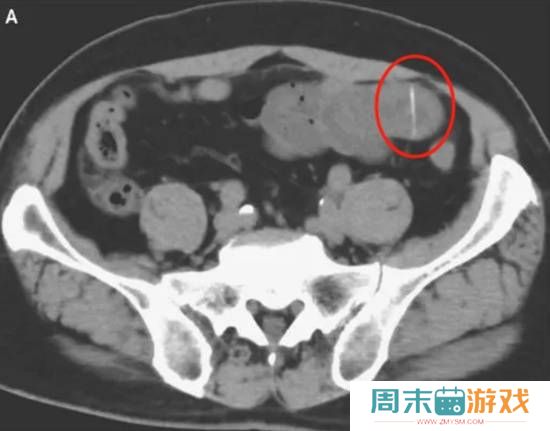

上一次,因为鱼刺让我震惊的案例是日本的一个男子,他的肠道被一根2厘米长的鱼刺刺了一个洞,最后只能切除部分小肠来治疗。